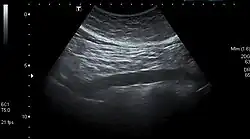

The standard aortic measurement on abdominal ultrasonography, such as used for abdominal aortic aneurysms, is between the outer margins of the aortic wall.[3] -

Abdominal aorta ultrasound